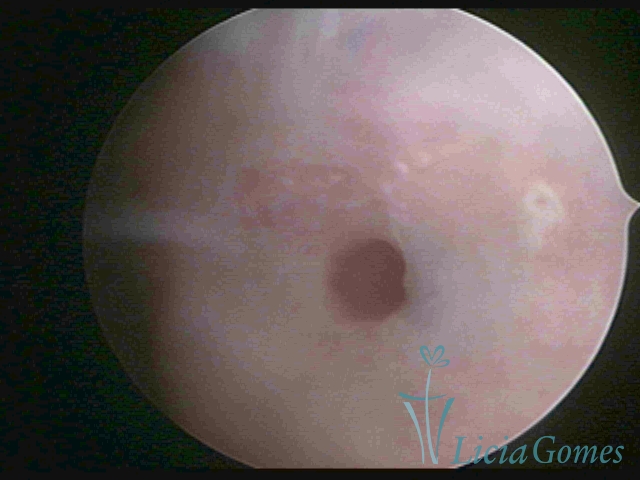

• Third part or upper section: presents the mucosa with a smooth, poorly vascularized surface